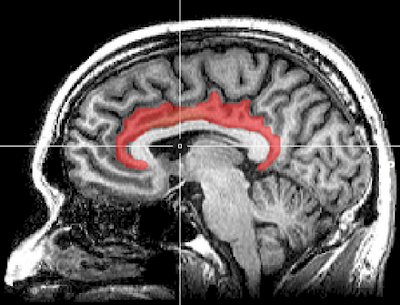

"بأمكانك اعتبار التلم داخل الفص الجداري intraparietal sulcus في الدماغ أنه يحتوي على قرصي تغيير محطات إذاعية في جهاز الراديو: أحدهما يضبط التركيز والآخر يضبط الفلترة،" قال ريتز. "في دراستنا، منطقة القشرة الحزامية الأمامية(5) في الدماغ تتبع ما يحدث مع النقاط التي تتحرك في دوامة سريعة . عندما تدرك القشرة الحزامية الأمامية، على سبيل المثال، أن الحركة تجعل المهمة أكثر صعوبة، فإنها توجه التلم داخل الجداري لضبط قرص الفلترة لخفض حساسيته للحركة.

![]() |

| القشرة الحزامية الأمامية: مصدر الصورة: الويكيبيديا |

"في السيناريو الذي تكون فيه النقاط الأرجوانية والخضراء تقريبًا 50/50، قد تقوم القشرة الحزامية الأمامية أيضًا بتوجيه التلم داخل الجداري لضبط قرص التركيز للرفع من مستوى الحساسية للون. الآن أصبحت متطقتا الدماغ ذات العلاقة أقل حساسية للحركة وأكثر حساسية للون المناسب، لذلك أصبح المشارك أكثر قدرة على اختيار اللون الصحيح.